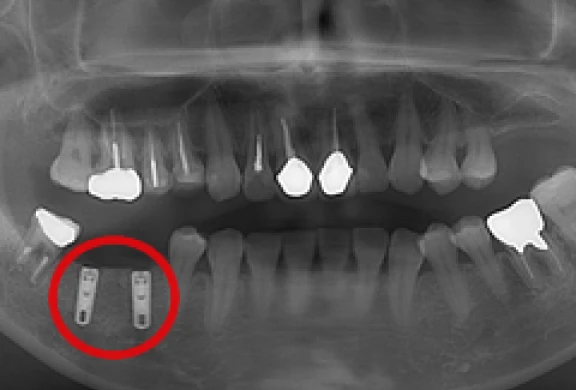

歯間部のインプラント

(2本)

-

(2本、上部構造の装着)